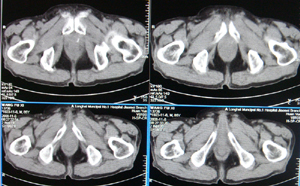

前列腺癌术后10余年,复查有无复发,请指教,图像做得不好,还望包涵

膀胱内可见占位,建议膀胱镜观察

连续看还是前列腺的病变,考虑复发.

应了解一下患者的具体手术方式,从所传图像上看未见明显异常(图像有点太小不便观看)。

前列腺增大,向上突入膀胱内,结合病史考虑前列腺癌复发可能。

图像太小,左侧膀胱壁似见不规则突起,前列腺突入膀胱,建议膀胱镜检查及前列腺增强检查。